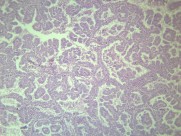

腺癌(adenocarcinoma)为涎腺上皮发生的恶性肿瘤,结构不一,但没有残留的多形性腺瘤的成分。腺癌占涎腺上皮性肿瘤的9%,属于涎腺恶性肿瘤中恶性程度较高的一种。

显微切片

肿瘤

腺癌

adenocarcinoma